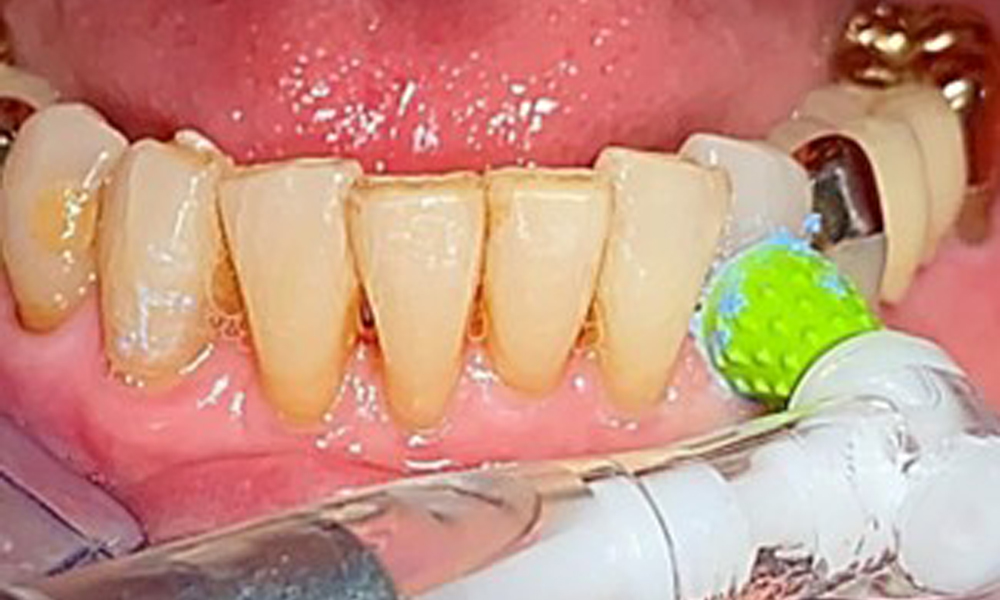

A single-tufted brush is specifically recommended for the telescopic prostheses (Fig. 8) and the patient should be advised on the appropriate interdental brush size (Fig. 9). The patient has been implementing these recommendations for intraoral hygiene at home for many years and was encouraged to continue during the professional preventive dental appointment.

An air polishing system should be used with low-abrasive powder to remove biofilm from the restoration margins, interdental areas and implant surfaces (Fig. 12). Selective polishing (Fig. 13) should be used to smooth any less sensitive areas, as this decreases bacterial reattachment (9).

Interdental cleaning with brushes (Fig. 9) or dental floss is just as important as cleaning the tongue.